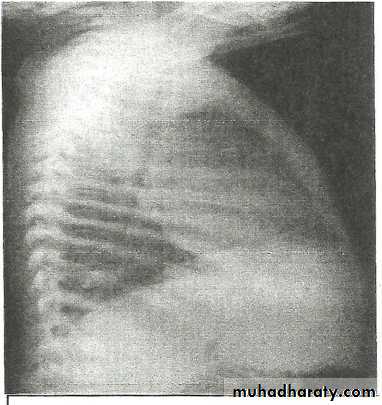

• Right lower lobe consolidation - Lat.

• The density lies posterior to fthe oblique issure- the position of the lower lobe.